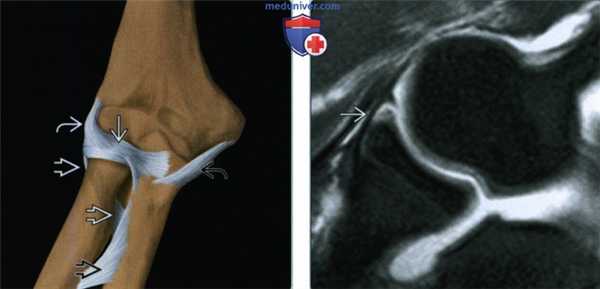

(Слева) На рисунке латеральной локтевой коллатеральной связки показана, что она начинается на латеральном надмыщелке плечевой кости, идет кзади от лучевой кости и прикрепляется дистально к гребню супинатора локтевой кости. Лучевая коллатеральная связка начинается непосредственно кпереди и прикрепляется к лучевой кости.

(Справа) На фронтальной МРТ PD ВИ виден ход нормальной латеральной локтевой коллатеральной связки. Латеральная локтевая коллатеральная связка отходит от латерального надмыщелка плечевой кости, обворачивается вокруг головки лучевой кости и прикрепляется к проксимальному концу локтевой кости.